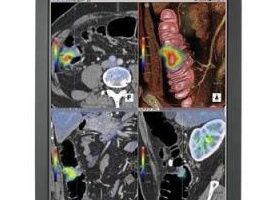

CT仿真內窺鏡成像:是螺旋CT一種新的三維重建技術,有人經過186例喉仿真內窺鏡的研究得出結論:利用它進行重建和圖像處理,可以充分顯示喉腔病變和周圍浸潤情況,且具有不用插管、無創傷性,副作用少,同時可多次觀察,達到類似纖維內窺鏡的檢查效果。有人在36例進行CT仿真內窺鏡成像胸部疾病患者的檢查中:螺旋CT氣管、主支氣管3維重建與CT仿真內窺鏡成像從檢查的無創傷性、圖像的直觀性和整體性以及CT仿真內窺鏡圖像與纖支鏡圖像的一致性,認為其有著良好的套用前景。同時也有人認為:CT仿真內窺鏡成像能清晰顯示上、中、下鼻甲及鼻道。在探討高解析度CT、三維重建、CT仿真內窺鏡成像等在中、內耳檢查的臨床套用中,薄層HRCT可較好地觀察中、內耳的細微結構,三維重建技術的圖像較二維圖像顯示得更加立體直觀,CT仿真內窺鏡成像可從耳的任何位置包括彎曲的竇腔內顯示前、中、後中耳的結構,且能從各個角度更好地顯示聽小骨。

是螺旋CT一種新的三維重建技術,無創傷性,副作用少。